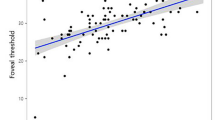

Table 2 demonstrates the associations between the macular thickness parameters and the ocular factors (including DFD, axial length, and refractive error). DFD was significantly correlated with all macular thickness parameters at a Bonferroni-corrected P value of 0.004 (0.05/12), with r ranging from −0.27 to −0.47, except for the temporal outer (r = −0.15, P = 0.089) and inferior outer(r = −0.22, P = 0.011) macular thickness. Axial length was mainly associated with the outer macular thickness parameters. This was less clear for the refractive error. Figure 2 shows the correlation between DFD and the summary macular thickness parameters. Age (r ranging from −0.08 to 0.06, all P > 0.3), signal strength (r ranging from −0.05 to 0.06, all P > 0.5), and visual field mean deviation (MD; r ranging from 0.01 to 0.11, all P > 0.1) did not correlate significantly with any of the macular parameters (within this group of subjects with a limited age range, signal strength range, and healthy eyes, that is, limited MD range). Eyes with β-PPA showed a thinner average macular thickness (273.7 versus 280.2 μm; P = 0.001) and a greater DFD (4.63 versus 4.53 mm; P = 0.002), compared to eyes without β-PPA. Table 3 presents the multivariable analysis. DFD, axial length, and gender were significantly associated with the average inner and outer macular thickness and the overall macular thickness; age and signal strength were not significant in the initial multivariable model and removed from the final model. Disc area and the presence of β-PPA were not significantly associated with any of the macular thickness measurements. Both DFD and gender were significantly associated with the central subfield thickness. There was no significant relationship between axial length and the central subfield thickness.

In order to remove the confounding effect of ocular magnification on the OCT scan area and DFD, a subgroup analysis was performed in eyes with axial length between 24 and 25 mm. Table 4 shows the results. Again, DFD was strongly associated with macular thickness; a larger DFD implies a thinner macula.

Disc-fovea distance has a significant inter—individual variability in healthy myopic eyes and is significantly associated with macular thickness. Eyes with a greater DFD have a lower average macular thickness and a lower central subfield thickness, independent of axial length and gender.

Variability in macular thickness in healthy eyes has been described previously13,14,15,16,17,18,19,20,21,22,23,24,25. Several factors, including age, axial length, and gender, have been reported to be associated with macular thickness13,14,15,16,17,18,19,20,21,22,23,24,25. A lower macular thickness has been observed in myopic eyes13,16,18, an effect that could be explained by stretching of the globe. Related to this, it has also been reported that a greater DFD is associated with a longer axial length26. Together this could suggest that the observed relationship between macular thickness and DFD is just an epiphenomenon of myopia. However, we found that DFD was independently associated with macular thickness, that is, not (only) through the effect of axial length. Macular thickness decreased typically 20–30 μm per mm increase in DFD (Tables 3 and 4; these analyses were adjusted for axial length), which corresponds to approximately 10 um per standard deviation of DFD (Table 1)26. As a result, a clinical assessment of macular thickness can be improved significantly by taking DFD into account. Importantly, it is easy to take DFD into account: unlike axial length, you don’t have to measure it separately because it can be measured from the OCT scan itself. Currently this can be done by using the built-in manual measurement tool of the OCT device; in the future this could be added to the software and normative database.